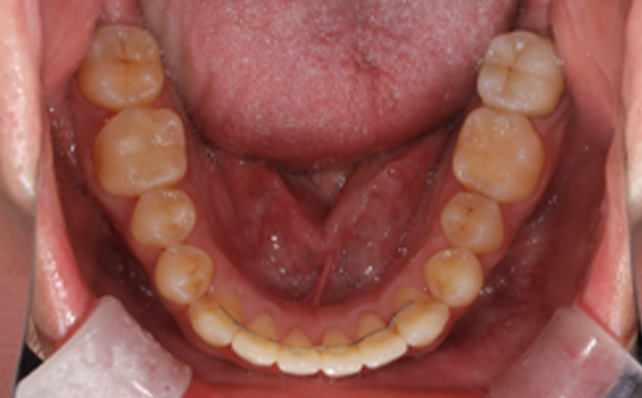

治療前